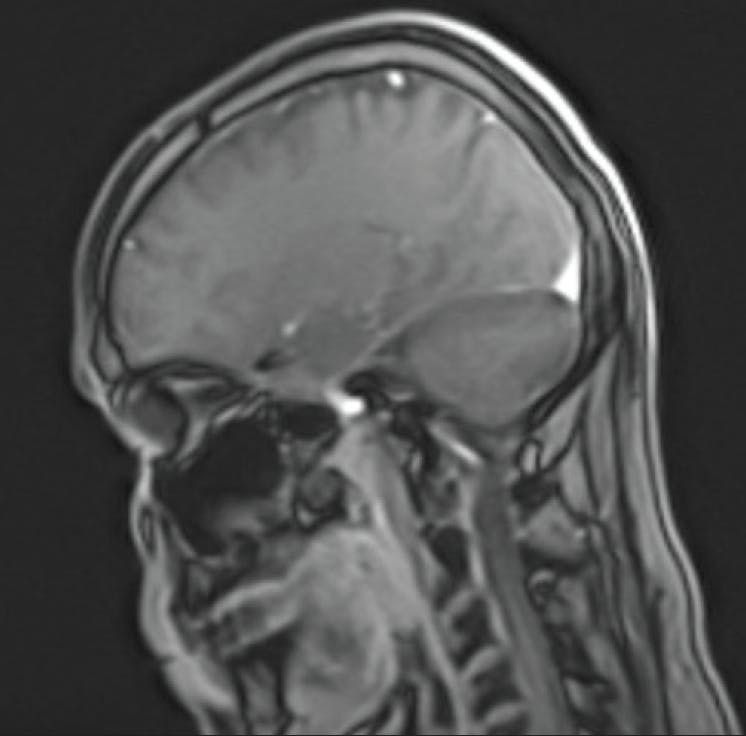

A 25-year-old female presented with complaints of soreness and missing parts of her vision in her left eye. Findings in her right eye were normal, but her left eye showed reduced visual acuity, an afferent pupillary defect, reduced color vision, pain on eye movement, and subtle optic nerve disc edema (Figure 3). I ordered an MRI of her brain with and without contrast, which revealed “multiple lesions exhibiting contrast enhancement suggesting active phase of demyelination” (Figure 4). Additionally, MRI of the orbits revealed “enhancement of the intraorbital segment of the left optic nerve, indicating active demyelination in the setting of multiple sclerosis.”